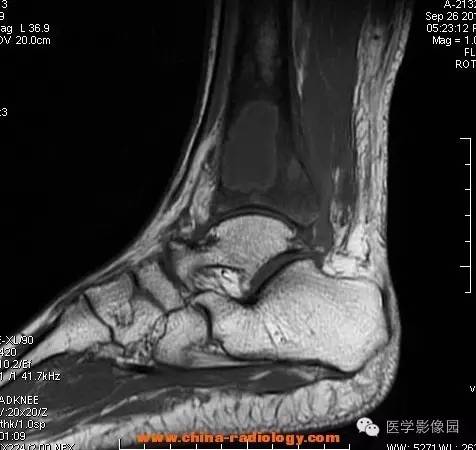

影像学表现:胫骨中下段干骺端不未规则形长T1长T2信号,T2WI见不完整环形稍低信号影,T2脂肪抑制低信号更明显,并见胫骨下段及踝关节后外侧软组织呈弥漫稍高信号,增强明显不均匀强化,增强见低信号环内有环形强化影。

影像学表现:表现为长骨干骺端有椭圆形密度减低区,边缘有清晰的骨质硬化,病变与邻近正常骨髓腔境界清楚。MRI上T1WI呈低信号,少数呈等信号,T2WI多为混杂高信号,增强扫描可见环状强化,强化的脓肿壁薄而均匀。